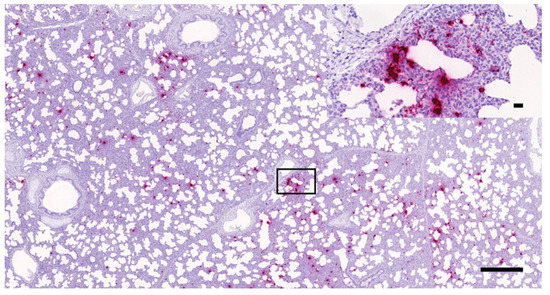

3.1. Histopathology and In Situ Hybridization